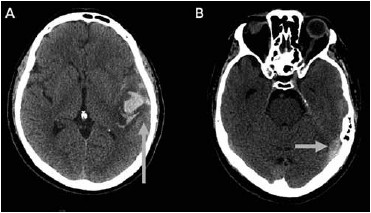

Homem, 60 anos, sem antecedentes prévios, foi admitido no pronto-socorro com quadro de afasia mista. Na admissão encontrava-se afebril, taquicárdico e pressão arterial de 210/103 mmHg. As imagens de tomografia de crânio realizadas estão a seguir. As setas indicam um sinal característico encontrado nas suspeitas de trombose venosa cerebral. Assinale a alternativa correta.

(Arquivo pessoal; imagem usada com autorização)